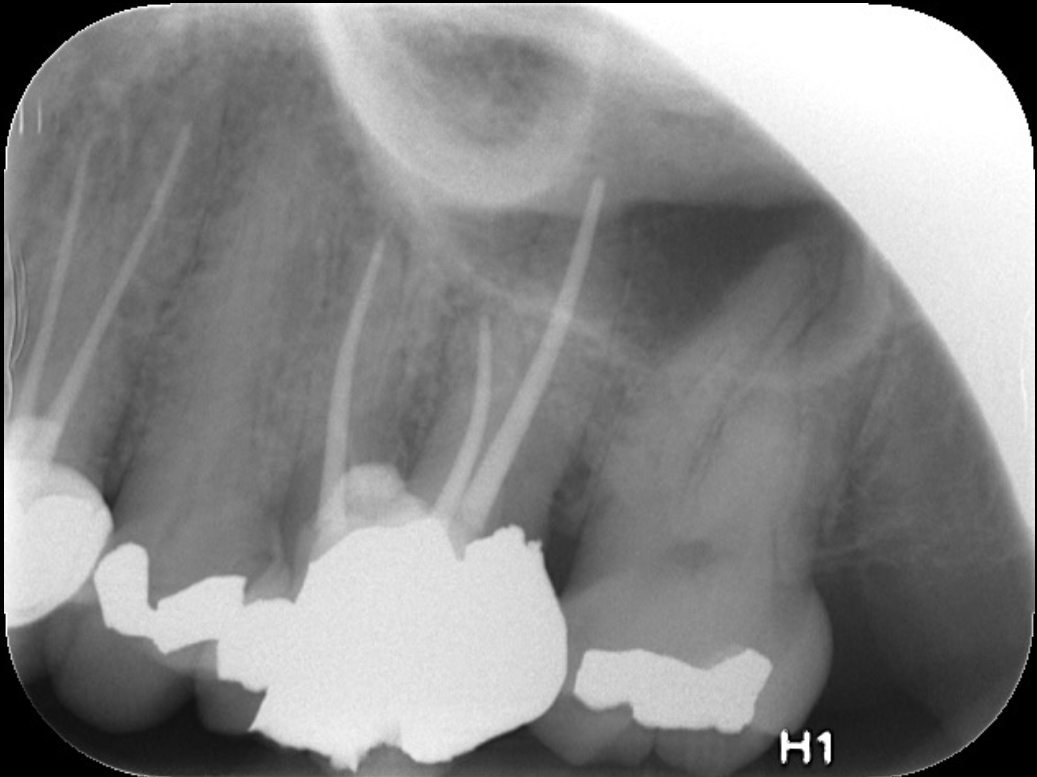

Clinical procedure: If apical bone loss is present (Figure 1) a collagen/gelatin sponge (eg, Gelfoam®, Pfizer Inc., www.pfizer.com) can be placed apically so that the MTA can be delivered to the desired working length. (Any other surgical resorbable sponge would also work, such as OraPlug® [Salvin Dental Specialties, www.salvin.com], Surgifoam® [Midwest Dental, www.mwdental.com], or Surgispon® [Aegis Lifesciences, www.surgispon.com]). This is done by taking a small piece (2 mm x 2 mm) of the resorbable sponge and pushing it down to and through the root apex with an endodontic file. Once this is done, MTA is packed down the canal with a custom-fitted cone. The clinician can use a rubber stopper on the gutta-percha cone to know the exact length of MTA placed in the apical third (Figure 2). Once the apical third is sealed with 3 mm to 5 mm of MTA, the remaining coronal canal space can be back-filled using a warm gutta-percha technique (Figure 3).

Fig 1. Preoperative radiograph showing apical bone loss.

Figure 1

Fig 2. MTA placed in the apical third.

Figure 2

Fig 3. Postoperative radiograph.

Figure 3